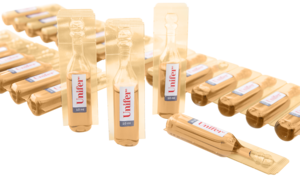

Первым препаратом этого направления стал Юнифер — водный раствор железа 2-х валентного в органической (хелатной) форме. Стабильность хелата Fe2+ в водном растворе с антиоксидантным комплексом обеспечивает быструю транспортировку, лучшее усвоение и переносимость препарата. Такой подход дает новые возможности в лечении железодефицитной анемии.

Компанией Менора Лабораториз разработаны современные методики для клинического применения препарата Юнифер в различных областях медицины, таких как гематология, гинекология, педиатрия, хирургия, онкология.